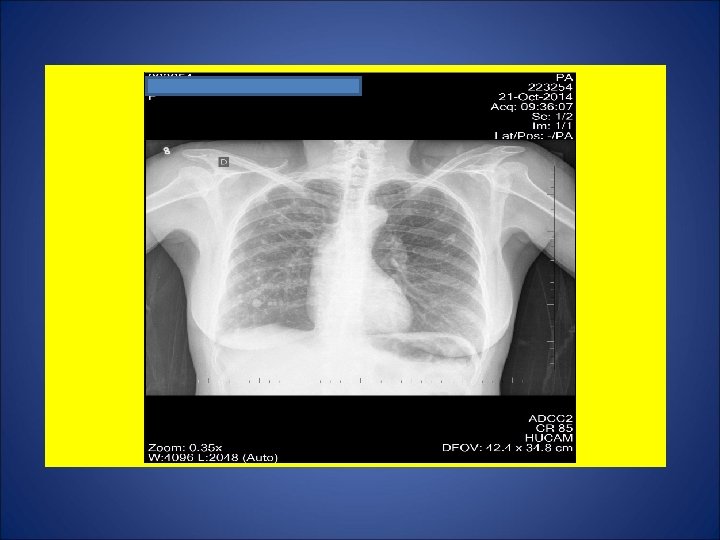

CASO 13, feminina, 78 anos, natural de Muqui (ES), residente em Cariacica (ES), viúva, pensionista. Tosse não produtiva há 2 meses. Negou episódios de escarros hemoptóicos e hemoptise. Em 24 set 14, foi levada ao pronto atendimento (PA) devido ao surgimento nessa data de dor torácica à direita em pontada. Realizada radiografia de tórax e prescrito amoxicilina 8/8 h, a qual fez uso irregular. Uma semana após, foi levada ao mesmo PA, sendo submetida a outra radiografia de tórax e prescrito outra medicação via oral 12/12 h. Fez uso por 7 dias. Retornou a esse PA, sendo iniciado ceftriaxone 2 g/dia por 7 dias. Nessa consulta, foi solicitado pesquisa de BAAR em escarro. Segundo a filha da paciente, há 4 meses a paciente apresenta hiporexia moderada. Durante os últimos 6 meses, perda de 10 Kg. Há mais de um ano, episódios de chieira e dispnéia. Diabetes mellitus há 10 anos. Em uso de metformina 850 mg/dia. Portadora de hipertensão arterial. Negou tabagismo e etilismo. Negou tuberculose prévia. Contato com caso vizinho tratado de tuberculose alguns anos atrás. HIV negativo. Ex. fisico: P=52 Kg, Altura= 1, 62 m, IMC= 19, 8 Kg/m 2 (normal), restante NDN. NÃO TEM MARCA de BCG em MSD.

ESCARROS ESPONT NEOS: 1º) 22/10/14: 7 m. L – SALIVA – 1: 00 h - BAC NEG – TRM M. tuberculosis DETECTADO - CULT em curso 2º) 22/10/14: 7 m. L – SALIVA – 25 min: BAC NEG –CULT em curso 3º) 23/10/14: 5 m. L – TURVO – 20 min: BAC NEG – CULT em curso